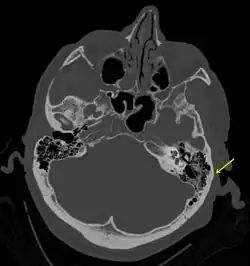

Ein Schädelbasisbruch (oder eine Schädelbasisfraktur) entsteht nach einer sehr starken Gewalteinwirkung im Kopfbereich, am häufigsten durch Verkehrsunfälle, und ist eine lebensbedrohliche Verletzung. Dabei werden knöcherne Strukturen der vorderen, mittleren oder seltener der hinteren Schädelgrube an der Schädelbasis verletzt. Die wichtigsten zwei Bruchformen sind die rhinobasale (Nase und Schädelbasis) oder frontobasale und die otobasale (Ohr und Schädelbasis) oder laterobasale Fraktur. Bei erster reicht der Bruchspalt in die Nasennebenhöhlen, letztere betrifft das Schläfenbein. Typisch ist der Austritt von Blut und Gehirnflüssigkeit aus Nase oder Ohren. Entweder durch das eigentliche Trauma oder auch durch sekundäre Einblutungen in das Gehirn sind gelegentlich Bewusstseinsstörungen oder neurologische Ausfallserscheinungen vorhanden (Commotio cerebri).

Die Diagnostik des Schädelbasisbruchs stützt sich auf bildgebende und laborchemische Verfahren. Das klassische Schädelröntgen in 3 Ebenen wird heutzutage zunehmend durch die Computertomographie (CT) abgelöst, die hochauflösend auch sehr kleine Risse im Schädel zuverlässig zeigen kann. Die Magnetresonanztomographie (MRT) stellt knöcherne Strukturen schlechter dar als die CT, sie wird daher nicht standardmäßig durchgeführt, kommt aber zur Anwendung, falls der Verdacht auf eine Gehirnverletzung besteht.